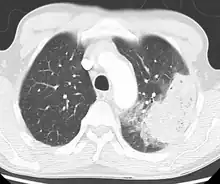

X-ray presentations of pneumonia may be classified as lobar pneumonia, bronchopneumonia, lobular pneumonia, and interstitial pneumonia.[75] Bacterial, community-acquired pneumonia classically show lung consolidation of one lung segmental lobe, which is known as lobar pneumonia.[42] However, findings may vary, and other patterns are common in other types of pneumonia.[42] Aspiration pneumonia may present with bilateral opacities primarily in the bases of the lungs and on the right side.[42] Radiographs of viral pneumonia may appear normal, appear hyper-inflated, have bilateral patchy areas, or present similar to bacterial pneumonia with lobar consolidation.[42] Radiologic findings may not be present in the early stages of the disease, especially in the presence of dehydration, or may be difficult to interpret in the obese or those with a history of lung disease.[24] Complications such as pleural effusion may also be found on chest radiographs. Laterolateral chest radiographs can increase the diagnostic accuracy of lung consolidation and pleural effusion.[41]

A CT scan can give additional information in indeterminate cases[42] and provide more details in those with an unclear chest radiograph (for example occult pneumonia in chronic obstructive pulmonary disease). They can be used to exclude pulmonary embolism and fungal pneumonia, and detect lung abscesses in those who are not responding to treatments.[41] However, CT scans are more expensive, have a higher dose of radiation, and cannot be done at bedside.[41]